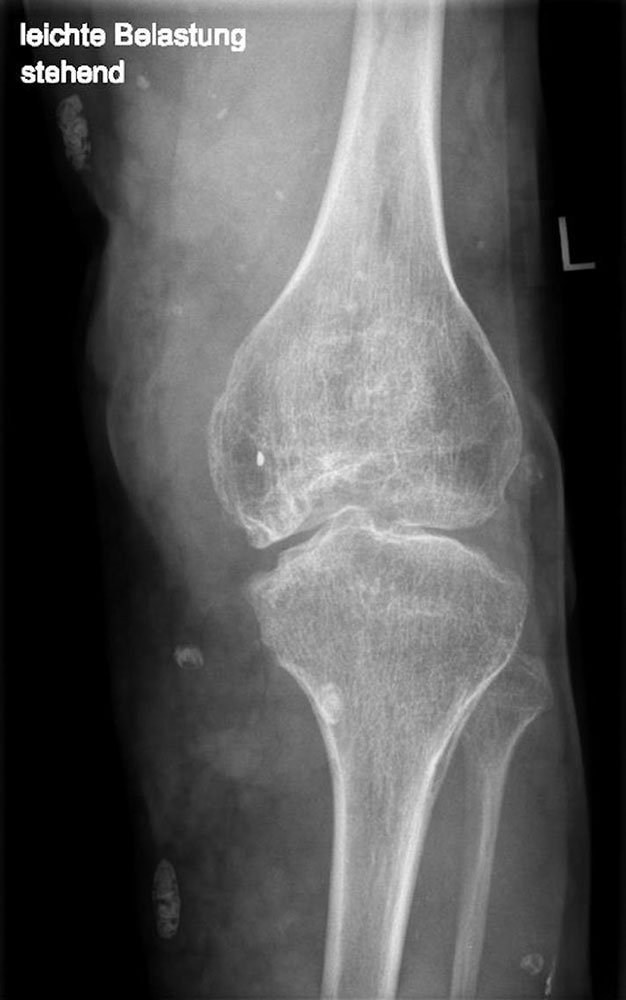

Störungen des Bewegungsapparates

Ausgedehnte intramuskuläre VM an den unteren Extremitäten und am Stamm können über eine asymmetrische Körperhaltung zu Fehlstellungen und Muskelschwäche mit erheblicher Einschränkung der Gehfähigkeit führen. Durch unsachgemäße oder zu radikale Therapiemaßnahmen kann es ebenfalls zu Langzeitstörungen der Mobilität kommen.

Bei Gelenk- und Knochenbeteiligung resultiert zudem eine erhöhte Frakturgefahr der oft begleitend dysplastischen Knochen, wobei dann die Bruchheilung erheblich verzögert erfolgt und es sogar zur Defektheilung kommen kann.

Die genannten Schäden am Bewegungsapparat sind dann ausgeprägter, wenn zusätzlich ein segmentaler Über- oder Unterwuchs vorliegt. Frühzeitig sollte dann ein Orthopäde, der über eine entsprechende Expertise verfügt, in die Betreuung eingebunden werden.